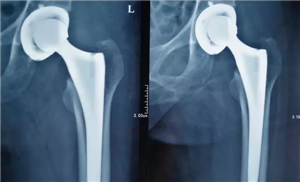

根据顾老太太的病情,胡玉华院长决定为其实施“左人工髋关节置换术”。在取得了顾老太太及她的家人同意后,手术于8月22日进行。在胡玉华院长、李龙付副主任、丁荣清医生、陆建玉医生的熟练操作、相互默契配合之下,一个半小时的手术十分成功。